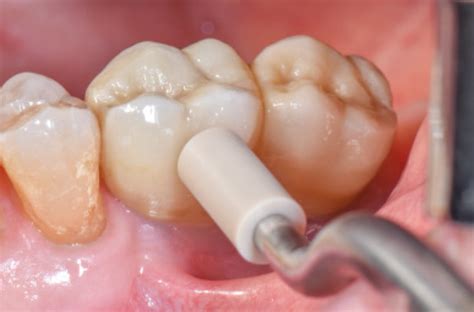

5. Pulizia del Substrato:Pulire accuratamente l'area da riparare utilizzando pomice o una pasta per profilassi priva di fluoro è un passaggio essenziale per un condizionamento efficace e per garantire una successiva adesione ottimale.

6. Preparazione del Rivestimento Ceramico:Utilizzando una fresa diamantata a grana fine, rimuovere lo strato di glasura lungo i margini da riparare e creare uno smusso. Questa procedura aumenta l'area superficiale disponibile per la reazione chimica tra l'acido fluoridrico, l'agente di accoppiamento silanico e la matrice vetrosa della ceramica, migliorando la formazione di legami silossanici. È fondamentale utilizzare abbondante acqua di raffreddamento durante questa fase per evitare il surriscaldamento della ceramica e la formazione di cricche.